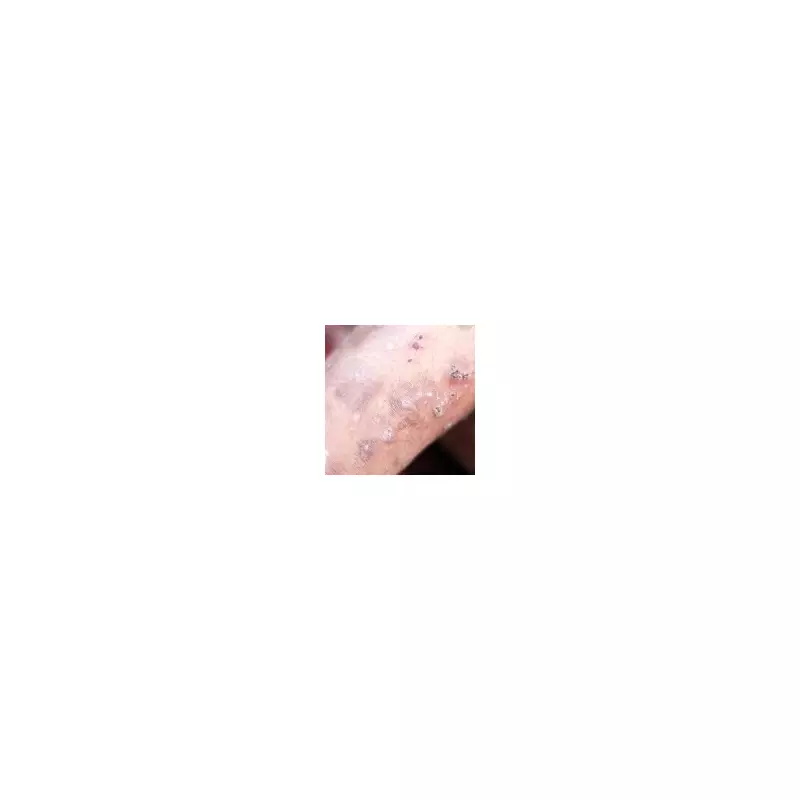

The parasitic infestation is caused by microscopic mites that burrow into the skin's surface, creating red, inflamed and crusty patches. Medical experts note that scabies is particularly problematic because it's often misdiagnosed or goes unnoticed during early stages, allowing carriers to spread it unknowingly.

Scabies presents as an intensely itchy rash with red spots appearing across the body, typically excluding the head and neck in most patients. The condition spreads through close skin contact, making school environments particularly vulnerable.

- Red spots and burrow tracks on the skin